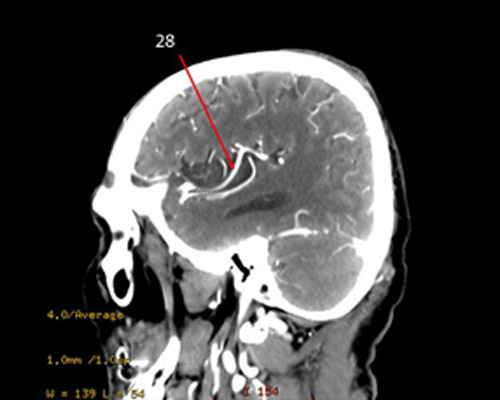

29?

anterior CA